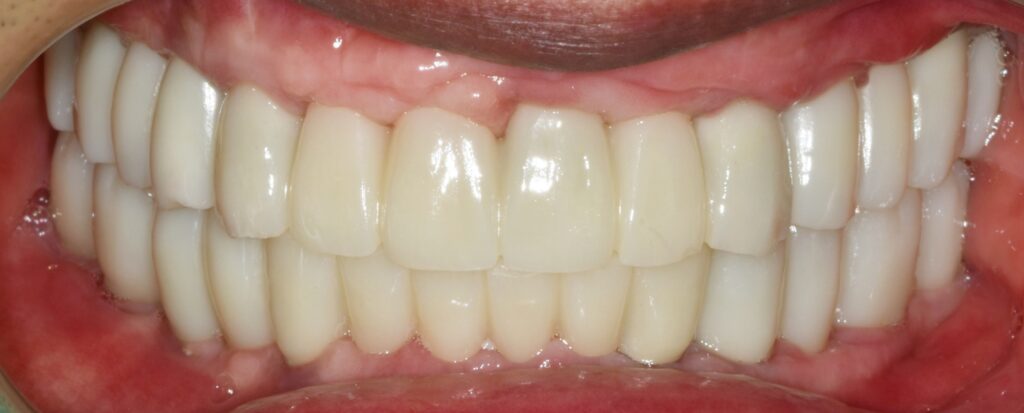

최종 보철물로 이행

임시 치아 기간을 대략 한 달에서 두 달 정도 갖고 모든 것이 다 좋다고 판단될 때 인상채득을 해서(본을 떠서) 최종 보철물로 이행을 해줍니다.

조화롭게 치료가 잘 된 모습입니다. 당연히 식사도 편하게 잘하시고 그 덕분에 생활에 활력이 넘치고 일이 잘 풀린다고 하셨습니다.

새 삶을 얻으신 것 같다고 후기 남겨주셨어요.^^